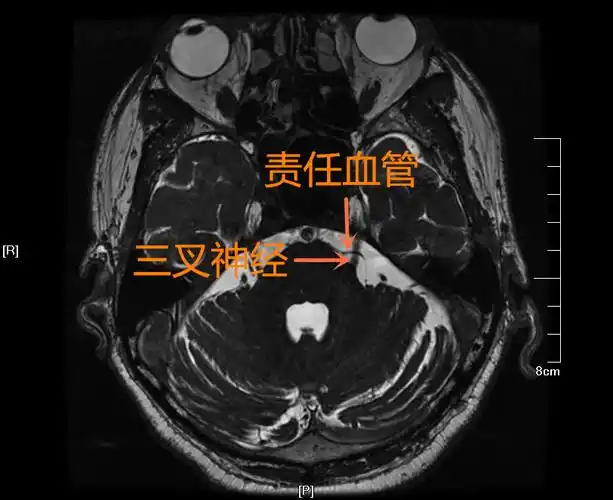

【病例-三叉神经痛】左侧面颊部疼痛4年,mvd术后疼痛消失